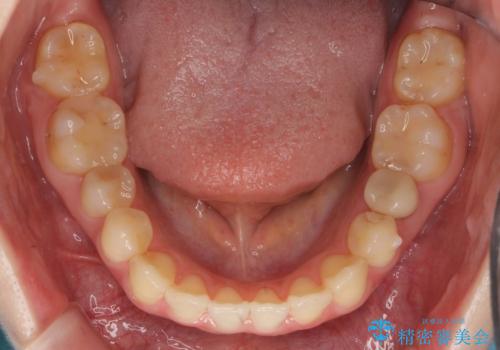

犬歯のねじれ 上の歯が引っ込んでいる

- 前歯の並びを気にして来院。

インビザラインで、上の前歯をやすり掛けして並べました。

途中妊娠、出産を挟み、患者様がアライナーがつけられない時期もあって治療自体は延長しました。